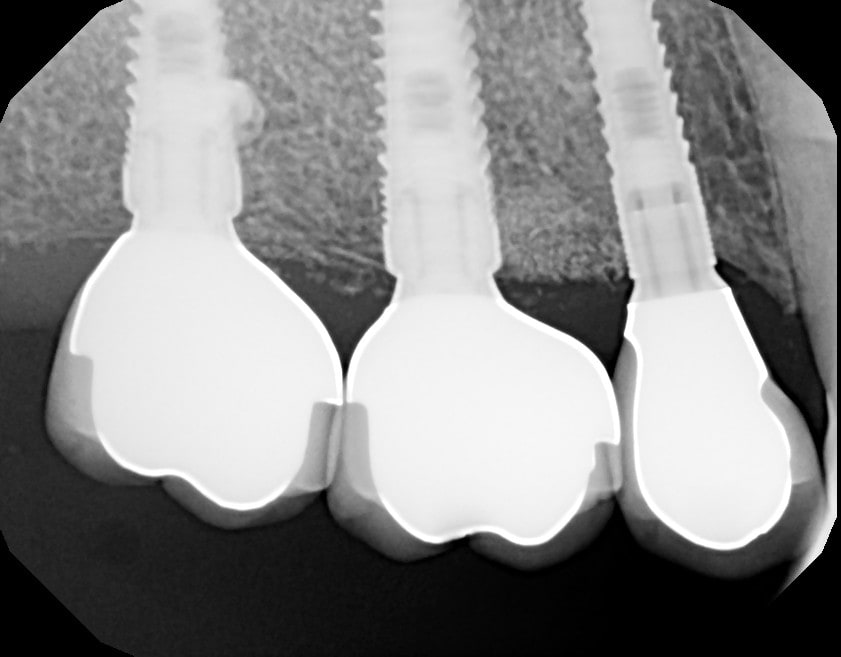

Pose couronnes zircone/céram transvissées

Nobel ASC : Angle Screw Chanel pour la 14, car axe pas top

Fermeture puits téflon-compo

Radio

15 et 16, piliers inclus avec l'InterActive

14 Pilier ASC de chez Nobel, compatible InterActive, avec rattrapage jusqu'à 25 degrés